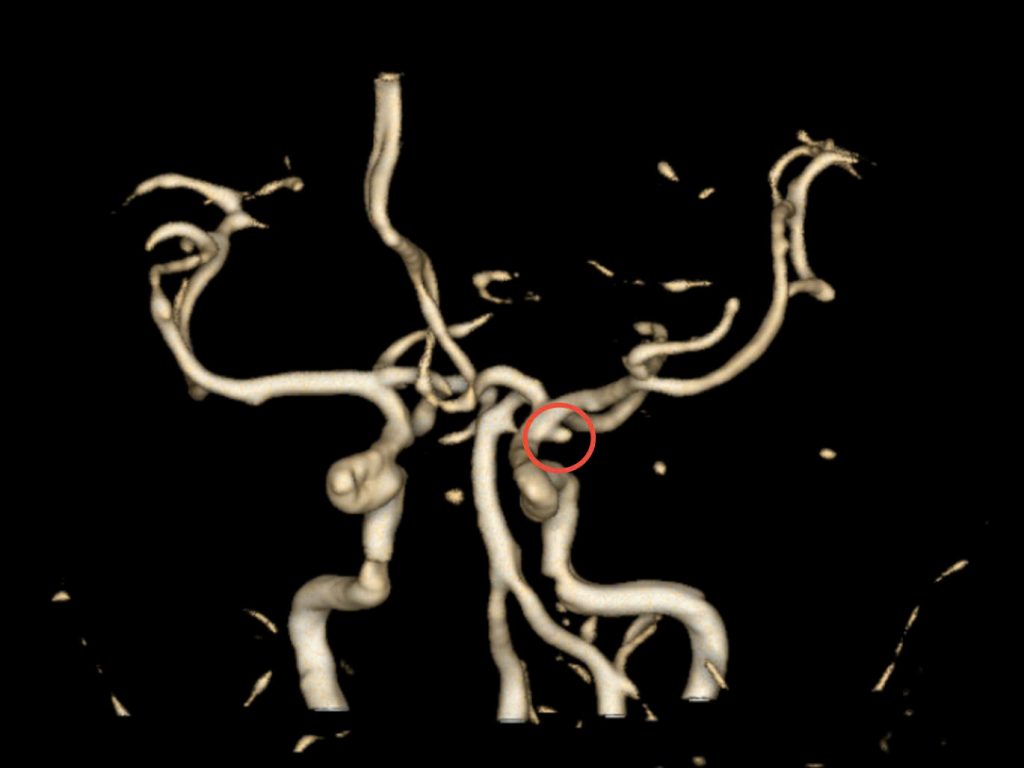

Với chẩn đoán trên, bệnh nhân được tiến hành chụp CT mạch máu não (CTA) và phát hiện một túi phình kích thước 7-8 mm ở động mạch cảnh trong đoạn thông sau, nằm tại một vị trí tương đối khó quan sát, gần sàn sọ và có dấu hiệu vỡ. Trước tình huống hết sức cấp bách, bệnh nhân được hội chẩn đa chuyên khoa gồm: Nội thần kinh, ê-kíp phẫu thuật thần kinh và can thiệp nội mạch. Sau đánh giá thống nhất, các bác sĩ quyết định tiến hành phẫu thuật khẩn cấp để xử lý túi phình cho bệnh nhân.

Vị trí túi phình trên phim CTA